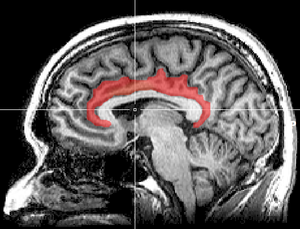

القشرة الحزامية cingulate cortex، تعرف أيضاً بالقشرة الحوفية، هي جزء من المخ يقع في الجانب الإنسي من القشرة المخية. القشرة الحزامية تشمل التلفيف الحزامي بأكمله، والذي يقع فوق الجسم السفني مباشرة، ويستمر حتى التلم الحزامي. القشرة الحزامية عادة ما تعتبر جزءاً من الفص الحوفي.